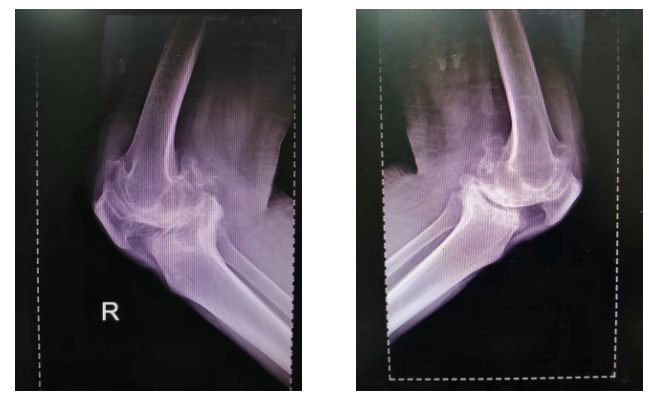

检 查:术前负重位X-ray显示双膝重度骨性关节炎合并屈曲内翻畸形。

术前影像:

术前正位

术前侧位